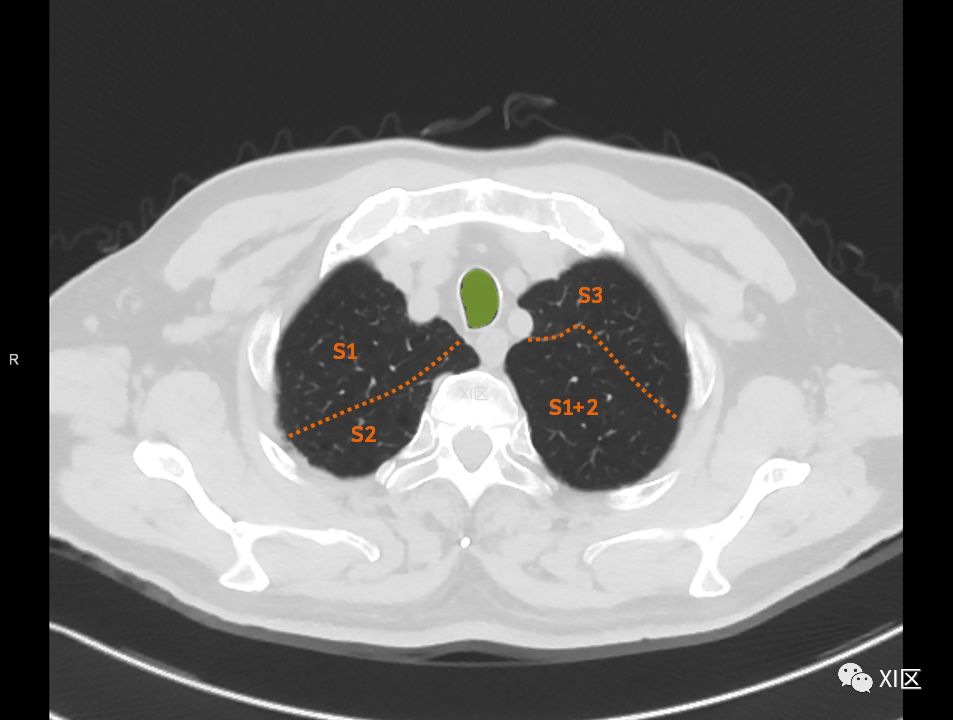

肺的断层分段示意图

在进行肺的分段时,可以上下观察浏览,沿着相应气管的走形可以更容易准确地进行分段。